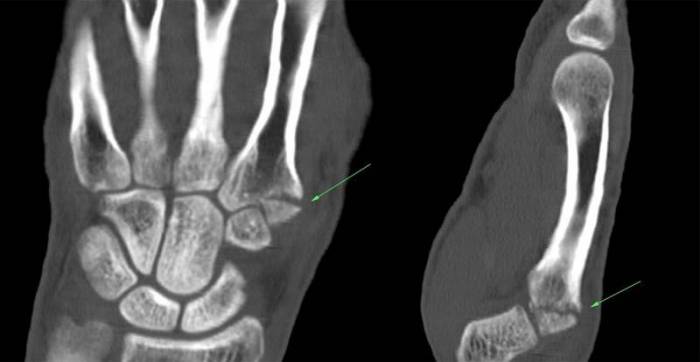

При КТ или проводится воздействие рентгеновского излучения большой мощности. Оно генерируется с помощью множества датчиков, хорошо концентрируется в костях и хрящах больного. Оно выделяет травмированные и поврежденные участки, показывает мелкие трещины, наросты и костные мозоли. Это хороший способ проведения срочной диагностики после операции по вживлению искусственного сустава кисти.

Лучезапястный сустав, запястье и кисть руки наиболее часто подвержены травмам и воспалительным заболеваниям. Повреждаться может кость, мышечная связка, сустав и сухожилия. Симптомы в области кисти указывают на инфекционные или воспалительные процессы, травмы и системные заболевания. Диагностика лучезапястного сустава и кисти проводится путем рентгенографии и магнитно-резонансной томографии. Первый метод плохо визуализирует патологические процессы в мягких тканях мышцах, связках, сосудах и подходит для предварительной диагностики костных патологий.